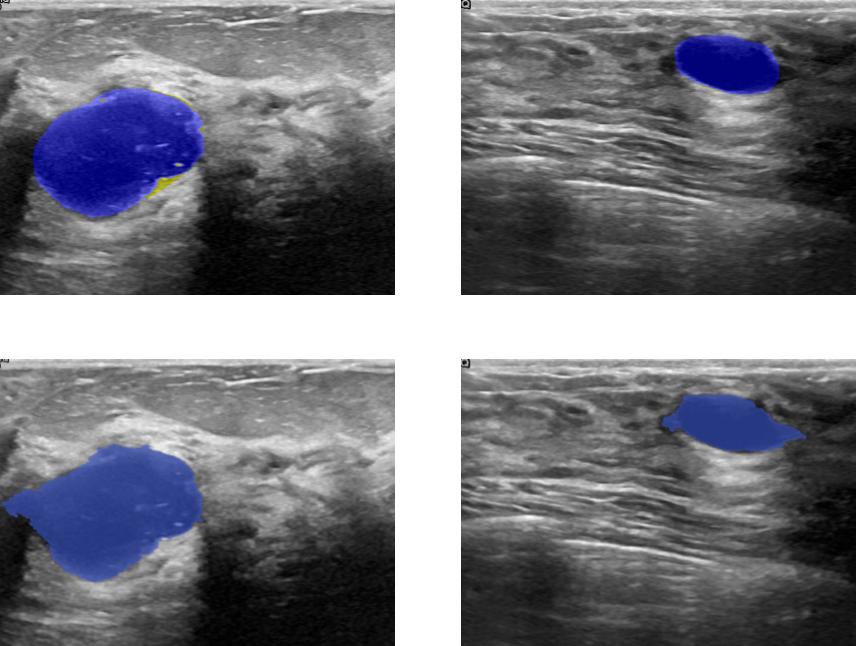

The figures below show the advantages and the limitation of our model in instance segmentation tasks. The Mask-RCNN[1] couldn’t capture the three dogs (top-left) and only segment two dogs as one and misclassify the remaining one as a horse while the three dogs are predicted appropriately but not well segmented due to occlusion inside the image. similarly for the top right prediction where the two men are well-segmented using our model. All in all, the Mask-RCNN[1] makes a lot of false alarms while our model predicts well the bounding boxes of objects. One limitation of our model is its lack of robustness to occlusion and hence it is not appropriate for predicting the mask of overlapping objects. Despite that, it is very efficient when it comes to segmenting the breast tumors since they are geologically not overlapping. The figures below shows two breast ultrasound scans with their corresponding predicted tumors (i.e, blue mask).

Benign tumors[43] share a number of features on ultrasound that indicate their benignity. In particular a round or oval shape , a large axis parallel to the skin, circumscribed margins or gently curving smooth lobulations , hyperechoic tissue in the case of solid tumors and anechoic content in the case of cysts and acoustic shadows in the edge. In contrast, malignant tumors[43] show specific features on ultrasound including, irregular shape with microlobulations or spiculations, a large axis that is not parallel to the skin, poorly defined margins, hypoechoic nodule or hetergenous echostructure and acoustic posterior shadowing. a visual analysis of the figures 4 and 5 prove that our model is able to capture the most relevant features we have already described.